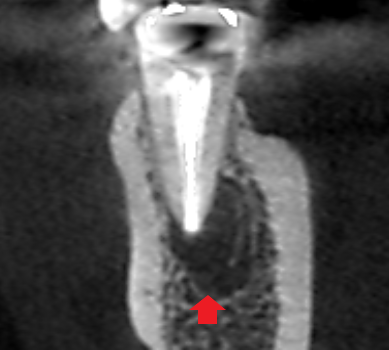

下顎第二小臼歯の初診時の冠状断のCT画像です。

赤い矢印の先に膿の影がみられます。膿は、画像では右側の舌側で拡がっていました。